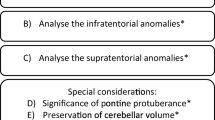

Supratentorial structures are affected, though less prominently. The group has not been clarified genetically or biochemically. An initial proposal for classification [6] is based on two types in which type 1 (PCH-1) associates PCH with spinal anterior horn cell degeneration [14, 33], while type 2 (PCH-2) associates PCH with clinical extrapyramidal involvement and absence of anterior horn degeneration [5–7, 37, 44]. Early detailed neuropathological reports on PCH [9, 10, 26] in retrospect may have been cases of PCH-2, but cannot be matched with the customary classification because of lack of clinical details. Neuropathological finding in PCH-2 [5, 7, 37, 41] is microencephaly with severe cerebellar and ventral pontine hypoplasia. Typical pathological findings are: (1) subtotal loss of ventral pontine neurons and transverse pontine fibers with preservation of long fiber tracts; (2) atrophy and hypoplasia of the cerebellar hemispheres with relative sparing of the vermis and flocculi, variable loss of Purkinje cells and internal granule cells and reduction in folial length; (3) patchy loss of cerebellar dentate neurons, with the remaining dentate neurons grouped in “islands”; (4) loss of neurons in the inferior olivary nucleus with the winding pattern essentially spared; (5) absence of the medullary arcuate nuclei. Findings in PCH-1 are essentially similar, but preservation of spinal anterior horn cells distinguishes PCH-2 from PCH-1 [14]. Microscopic supratentorial findings in PCH-2 are non-specific with neuronal loss in various compartments, including the cerebral cortex, while myelin and myelination remain unaffected. Ultrastructural findings in a single reported neocortical biopsy are progressive neuronal loss in all layers and a peculiar degeneration in neurons in all layers that appear to start with patches of darkened endoplasmic reticulum [5]. Diagnosis during life is based on a combination of findings on MRI (Fig. 1), a profile of clinical neurological deficits that includes severe cognitive delay, swallowing disturbance and chorea/dystonia (less often, spasticity), exclusion of metabolic and chromosomal disorders with a similar MRI pattern and a family history compatible with autosomal recessive inheritance. In typical cases, behavioral and motor development is almost stagnant from the beginning, with onset of chorea/dystonia during the first year and progressive microcephaly [7, 44]. Differential diagnosis requires exclusion of glycosylation disorders, especially congenital disorder of glycosylation type 1A (CDG1A) [2, 21, 23] and Muscle-Eye-Brain disease [16, 29], sequelae of extreme prematurity [28] and chromosomal disorders [4]. Overlapping neuropathological features exist between PCH-2 and olivopontocerebellar hypoplasia (OPCH), a more severe disorder with an essentially similar combination of hypoplasia and degeneration affecting the hindbrain [3, 11, 18, 35]. Autosomal recessive inheritance in OPCH is suggested by its recurrence pattern in families. Clinical findings are variable, but include such indicators of prenatal onset as polyhydramnios and contractures. Its main structural features are severe cerebellar hypoplasia with emphasis on the hemispheres, absence of neurons in the ventral pons, subtotal absence of cerebellar dentate nuclei, diminished or absent olivary winding and absence of spinal anterior horn involvement. In a recent PCH classification, the original types 1 and 2 have remained identical, while olivopontocerebellar hypoplasia has become type 4, PCH-4 [36]. Type 3, with optic atrophy as its main distinguishing clinical feature [38], has not been studied neuropathologically yet, while type 5 until now is represented by a single family. The number of papers addressing the neuropathology of PCH-2 with sufficient clinical detail to support a type 2 classification is limited [5, 37, 41] and results of immunohistochemistry have not been reported yet. The aim of the present report is to provide a range of pathological findings based on a series of six autopsies with ages at death varying between 15 months and 22 years and to provide an update on neurodegenerative features using more specific staining techniques. Special attention is given to variability in cerebellar degeneration, degenerative changes in pons and lower brainstem and the types of astroglial and microglial reaction. Three patients (no. 4, 5, 6) originate from an area with a high degree of intermarriage and are related by genealogy. A case of olivopontocerebellar hypoplasia (PCH-4) is included for comparison of its neuropathology to PCH-2.

The cerebellar hemispheres are severely affected in all. On macroscopic examination, all major lobes are reduced in width and dorsoventrally flattened. Size was best preserved in the transverse plane. This asymmetric diminution in size and the relative sparing of the vermis lend the cerebella a butterfly or batwing aspect (Fig. 1b). Four of the six cerebella (cases 2, 4–6) are sectioned perpendicular to the folia with the line of the sectioning running from the culmen to the posterior pole. These sections include the flocculus. In two cases (1, 3), transverse sections of hemispheres and vermis are prepared. Low magnification (Fig. 3) shows the diminished size of the cerebellar hemispheres, folial shortening and diminished number of folial branches compared to a control (Fig. 3a, b). In the most affected case (Fig. 3g, h), no branches are seen at all, while in a less affected case folial branches are reduced to two or less (Fig. 3e, f). The other cerebella displayed regular folial branching (Fig. 3c, d), though less in quantity than the control specimen (Fig. 3a, b).